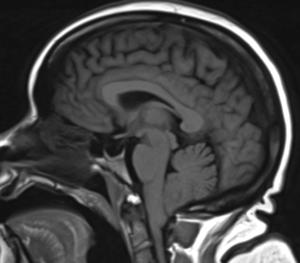

52-year-old female with vertigo, headache, tinnitus, eye twitching, and general instability while walking.